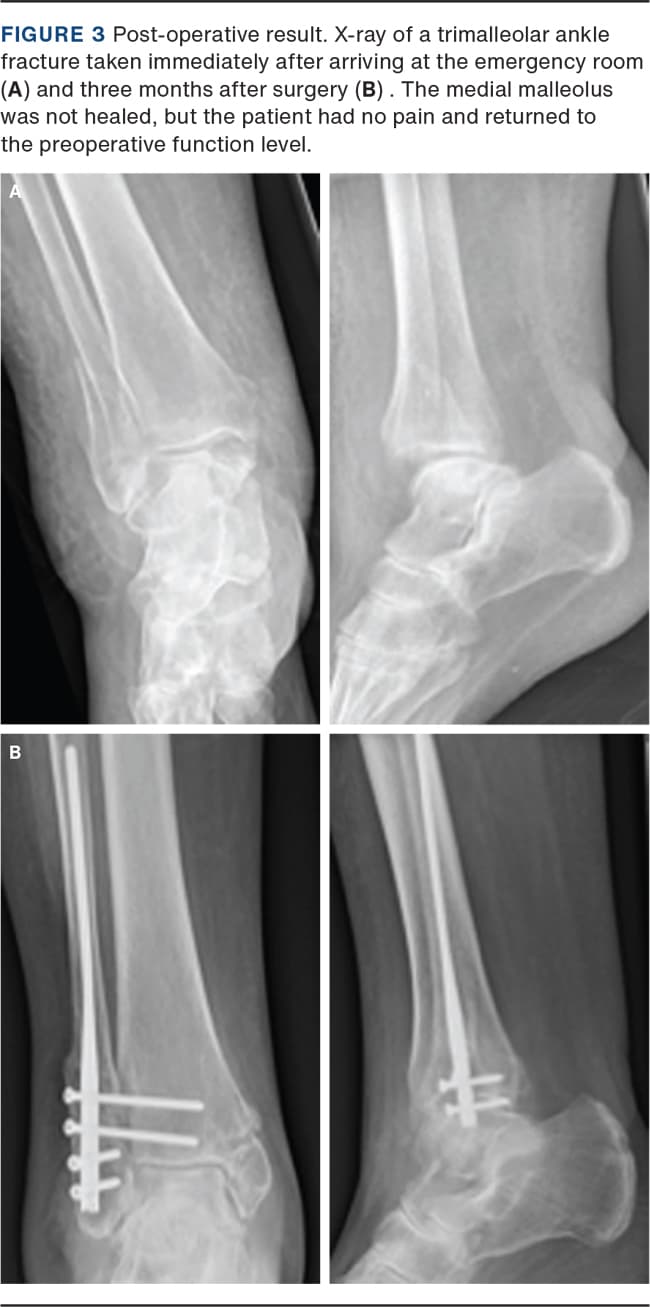

A total of 32 patients were included in this analysis with a mean follow-up period of 8.3 months (range: 3-46 months). Fracture healing (Figure 3) was observed in 93.7% of the lateral malleolus and in 50% of the medial malleolus at the last radiographic follow-up.